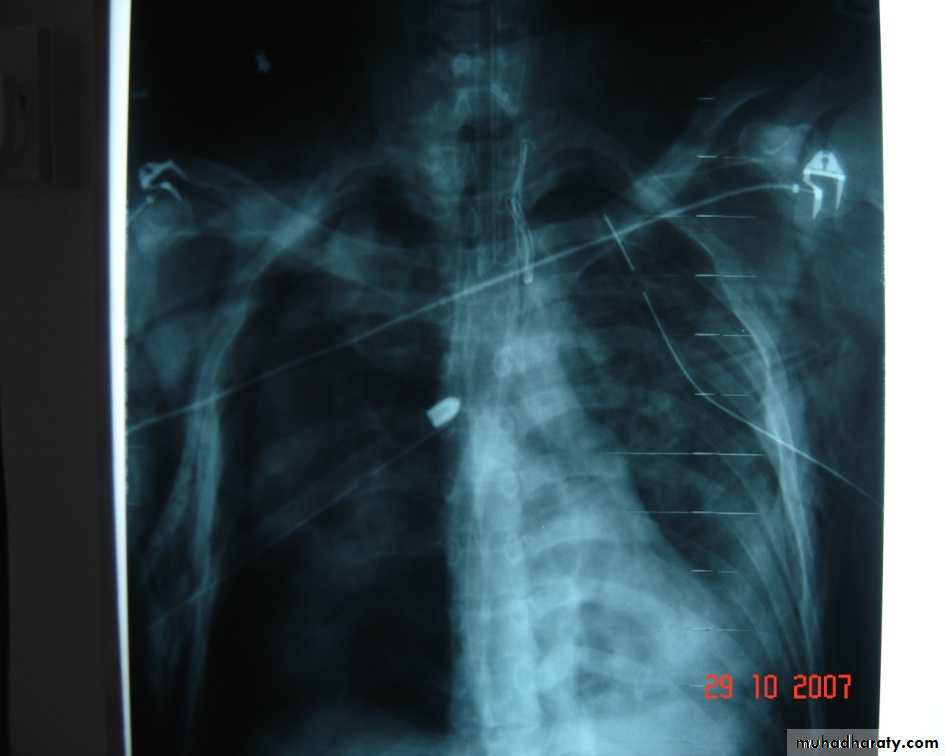

• 3-Pleurl injuries Can lead toA-Pneumothorax which can be partial or complete closed or open sucking or tension pnemothorax . B-Haemothorax may be mild or severe and may be with pneumothorax

Collapsed lungTraumatic haemothorax

• 4-Pulmonary injuriesTrauma can lead to pulmonary contusion with interstitial edema which may lead to consolidation of the lung tissues and can be manage by antibiotics administration and clearing of secretion